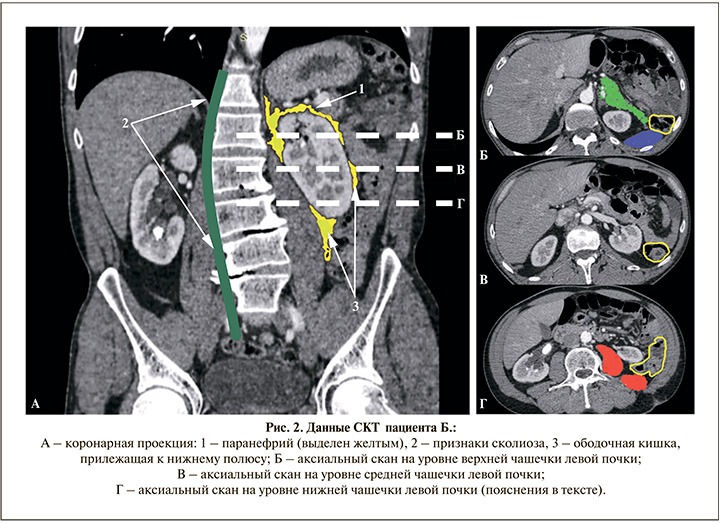

К очевидным факторам риска ранения ободочной кишки стоит отнести левосторонний доступ, наличие сколиоза и небольшое количество паранефральной жировой клетчатки (рис. 2а, 1-3). Более детально разберем синтопию на уровне верхней (рис. 2а-b), средней (рис. 2а-с) и нижней (рис. 2а-d) групп чашечек. Аксиальный срез на уровне верхней группы чашечек (рис. 2b): ободочная кишка (желтый контур) вне зоны интереса, тогда как по дорсальной поверхности почка интерпозирована селезенкой (закрашена синим), а по переднелатеральной поверхности – хвостом и телом поджелудочной железы. Риск повреждения последних достаточно высок при выборе данного доступа, и такие наблюдения описаны в литературе. Зона средней группы чашечек: на аксиальном скане (рис. 2с) видно, что до 50% пункционного окна уже занято ободочной кишкой (желтый контур). Уровень нижней группы чашечек характеризуется тем, что дорсальная поверхность и медиальный край почки экранированы mm. psoas major и iliacus sin. (закрашены красным), к оставшейся дорсолатеральной поверхности прилежит ободочная кишка (желтый контур). Нужно принять во внимание, что СКТ выполнено в положении на спине, а перкутанное вмешательство мы проводили в pron-позиции, что, как отмечено выше, повышает вероятность ретроренальной ободочной кишки [19]. Таким образом, пункция через ободочную кишку у данного пациента была предопределена, а ввиду достаточной редкости такого осложнения (это первое более чем на 1693 перкутанные нефролитотомии, что без учета перкутанных нефростомий составило около 0,6‰) мы вряд ли смогли бы актуализировать приведенные выше факторы риска и при наличии СКТ на дооперационном этапе.